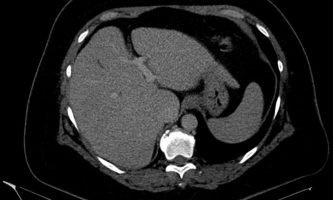

Independiente de su patrón de presentación, no condicionan cambios del parénquima luego de la administración de contraste endovenoso, no obstante igualmente se utiliza el gadolinio como medio de contraste para descartar otras entidades que puedan simular esta patología. La TC no suele aportar datos concluyentes cuando los focos de esteatosis son de pequeño tamaño y de bajo contenido graso, no logrando una adecuada diferenciación en su atenuación.7-8 (fig. 14)